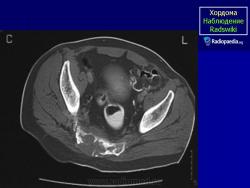

Случай 2: sacrococcygeal

Случай 8: sacrococcygeal

Случай 10: sacrococcygeal

Случай 12: sacrococcygeal

Случай 15: рецидивирующий sacrococcygeal